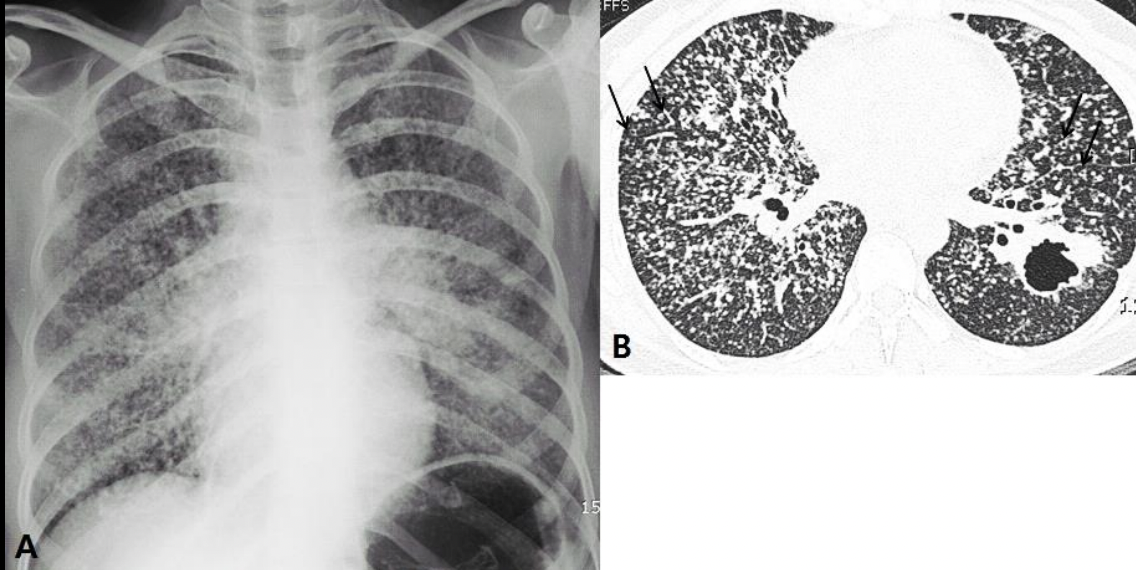

Miliar

Miliar: DESASTRE